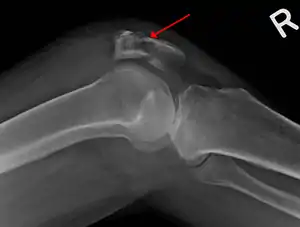

![]() | |

| A fracture of the patella seen on a lateral view | |